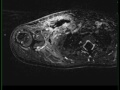

Right Clavicle Osteomyelitis and Subperiosteal Abscess

8-year-old female with history of right shoulder pain, limited range of motion, fever and leukocytosis. On physical examination, there is palpable fullness within the right supraclavicular region. There is a large region of T1 isointense signal to skeletal muscle within the supraclavicular fossa and base of the neck on the right. There is replacement of the normal marrow fat signal with a large confluent region of STIR hyperintense signal in the clavicle medullary space and surrounding soft tissues. There is a drainable fluid collection at the posteroinferior aspect of the right clavicle with peripheral enhancement on the post contrast images. Findings are compatible with clavicular osteomyelitis with a subpereosteal abscess. The most common site of infection in pediatric patients is at the ends of long bones where there is increased blood flow and altered flow dynamics. Staph aureus is the most common agent of infection.